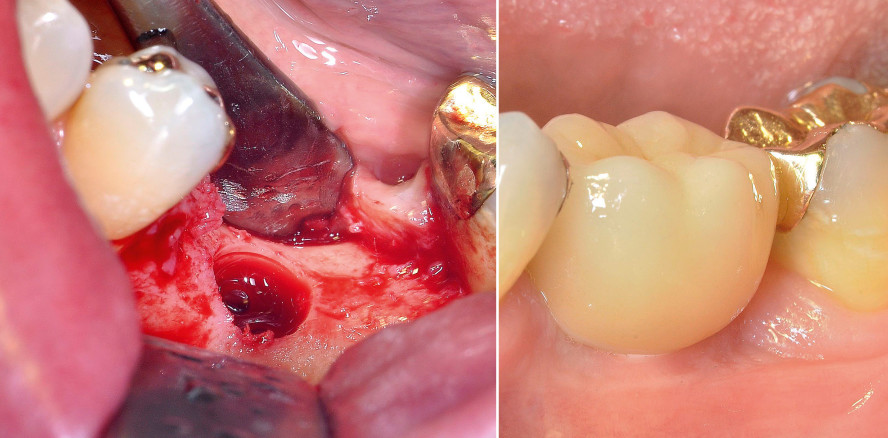

Ein 55-jähriger Patient benötigte den Ersatz des vor Jahren endodontisch behandelten Zahns 36, nachdem dieser periradikuläre Osteolysen durch einen Wurzellängsriss entwickelt hatte und entfernt werden musste. Die knöcherne Regeneration verlief verzögert. Nach Feststellung eines Vitamin-D3-Mangels und einer daraufhin begonnenen angemessenen Substitution stabilisierte sich die Knochenheilung. Die vorhandene Alveolarfortsatzbreite erwies sich klinisch als ausreichend für ein Implantat mit 5,5 mm Durchmesser. Die Implantatlänge von 10 mm wurde mittels eines Zahnfilms mit Rasterfolie festgelegt.

Anfang Dezember 2017 wurde die Insertion mithilfe einer Bohrschablone dreidimensional ausgerichtet durchgeführt. Hierbei wurde das vom Hersteller empfohlene Bohrprotokoll eingehalten. Beim Gewindeschnitt ist auf eine exakte Präparation zu achten, damit das Implantat mit einem empfohlenen Drehmoment von 20 bis 30 Ncm primärstabil verankert und die gewünschte vertikale Versenkung erreicht wird. In der Regel wird eine Insertion von Hand mit maximal 15/min durchgeführt, wobei das Implantat auf 0,6 bis 1,6 mm suprakrestal versenkt wird. Das Drehmoment wird aufgrund des konischen Implantatdesigns erst bei den letzten zwei Umdrehungen aufgebaut. Eine Versenkung auf nahezu Knochenniveau ist im ästhetischen Bereich anzustreben, um die spätere Aufbaustruktur gingival gedeckt zu platzieren. Für die bevorzugte geschlossene Einheilung wird der Mukoperiostlappen über dem Implantat speicheldicht vernäht. Die Implantatpositionierung wurde postoperativ röntgenologisch überprüft. Die Einheilung des inserierten Implantats verlief komplikationslos. Nach fünf Monaten erfolgten die Freilegung des osseointegrierten Implantats und das Einbringen eines Gingivaformers zur Abheilung der periimplantären Mukosa.